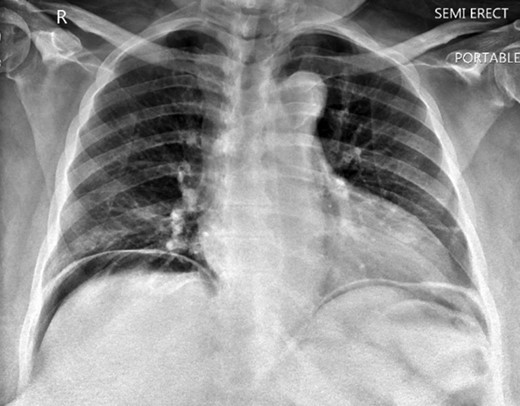

A 63-year-old African American female presented with complaints of abdominal pain located more in the right lower quadrant and multiple episodes of vomiting for the past 4 days. She had a history significant for ventral hernias and past surgical history of two myomectomies. Physical exam demonstrated right upper and right lower abdominal tenderness and peritoneal signs. Patient had fever and tachycardia. Chest x ray showed free air under the diaphragm (Fig. 1). Computer tomography revealed pneumoperitoneum and alarge gas containing collection in the pelvis measuring 13.6 Ă— 8.8 cm2. This was in close proximity to the sigmoid colon which appeared thickened, and extending to the right adnexal region (Fig. 2A and B). Laboratory results showed white blood cell count 28.7 Ă— 103/ ÎĽL, 93% neutrophils. The patient was taken to the operating room for exploratory laparotomy with the presumptive diagnosis of perforated sigmoid diverticulitis.